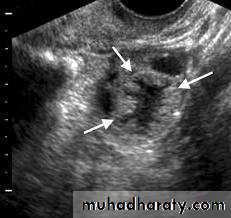

After ovulation, the granulosa cells and theca interna of the ovulated follicle reorganize to form a larger temporary endocrine gland, the corpus luteum (yellowish body), in the ovarian cortex.Corpus Luteum

Ovulation causes the collapse and folding of the granulosa and thecal layers of the follicle's wall and blood from disrupted capillaries typically accumulates as a clot in the former antrum..Corpus Luteum

Corpus Luteum of pregnancy